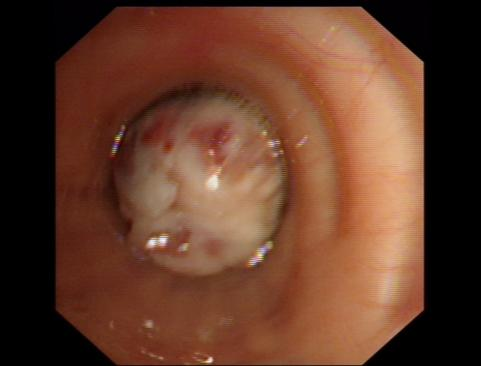

术后

术中剪影

麻醉成功后,佘巍巍博士娴熟地为患者插入了硬镜,然后配合电子支气管镜下电圈套器切除、冷冻冻取、活检钳钳除及氩气刀等多种手段对肿瘤进行切除,历时30分钟左右,肿瘤完全切除,左侧的主支气管恢复通畅。术后,患者呼吸困难症状减轻,次日就可以自如的下床活动且没有明显气喘不适,复查肺部CT和气管镜示左侧气道通畅,左下肺已经复张,为患者后续治疗争取到宝贵的时间。